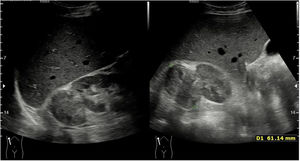

Tumor vesicalEl carcinoma vesical es el segundo cáncer urotelial más frecuente, después de cáncer de próstata. Es mucho más frecuente en varones y el factor de riesgo más importante es el tabaquismo. Además, son tumores con mucha frecuencia multifocales y con un índice de recidiva muy alto. También se puede detectar otros tipos de tumores vesicales como el carcinoma escamoso o el adenocarcinoma, pero son menos frecuentes.

Normalmente ante un paciente con hematuria en el que sospechamos tumor vesical se debe realizar una adecuada exploración física y solicitar analítica de orina, ecografía y cistoscopia.

Para poder realizar adecuadamente la ecografía es necesario una repleción vesical de al menos 200-250cc para poder visualizar correctamente toda la pared vesical. Con la ecografía podemos definir la localización del tumor y el tamaño. Los tumores más difíciles de visualizar son aquellos situados en el cuello de la vejiga o en la pared anterior, mientras que son muy fácilmente visualizables los tumores de la pared posterior o lateral. Con respecto al tamaño es importante conocer que los tumores inferiores a 5mm son difíciles de visualizar.

Los tumores vesicales se observan como lesiones sólidas, generalmente polipoideas, dependientes de pared, que no se movilizan con los cambios posturales del paciente (fig. 5).

Una vez que se detecta la lesión sólida de crecimiento intraluminal es importante utilizar el Doppler color para ver si presenta vascularización, pero en caso de tener Doppler positivo no indica más criterios de malignidad ni de agresividad del tumor16.